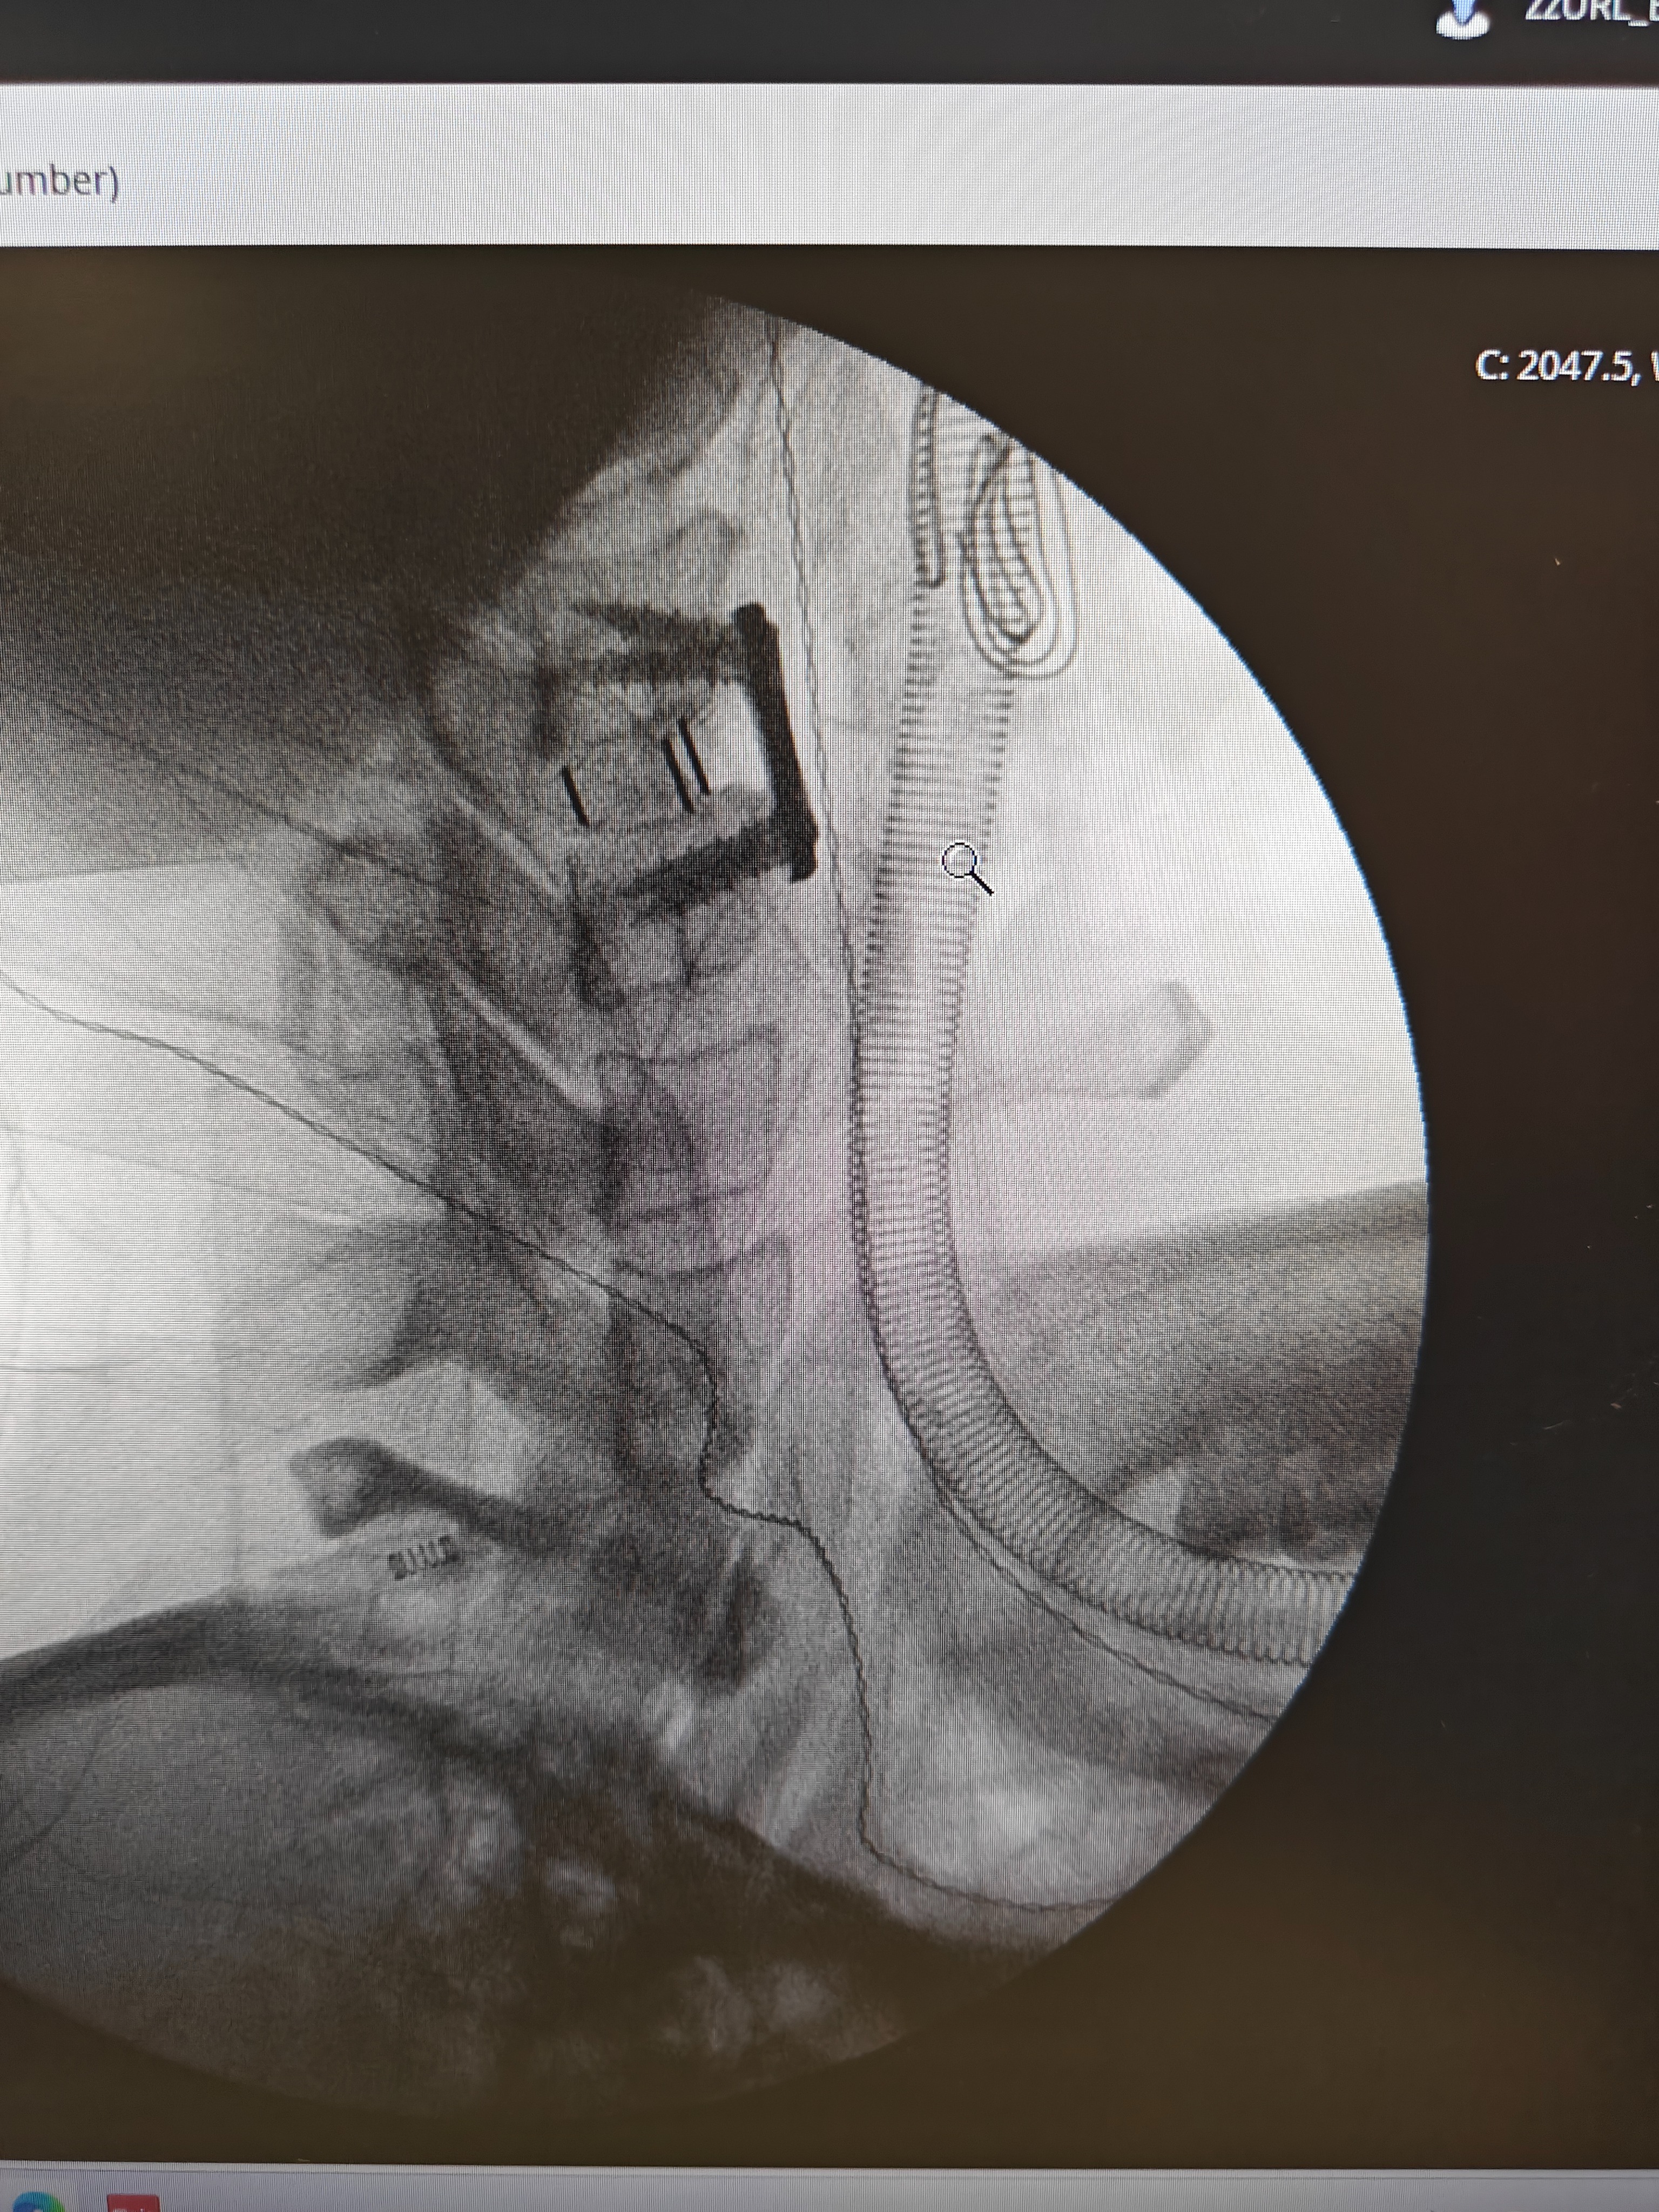

I am currently in critical care in hospital with a severe spinal cord injury and my life has been torn apart. I am so scared about what my future will be from now on.